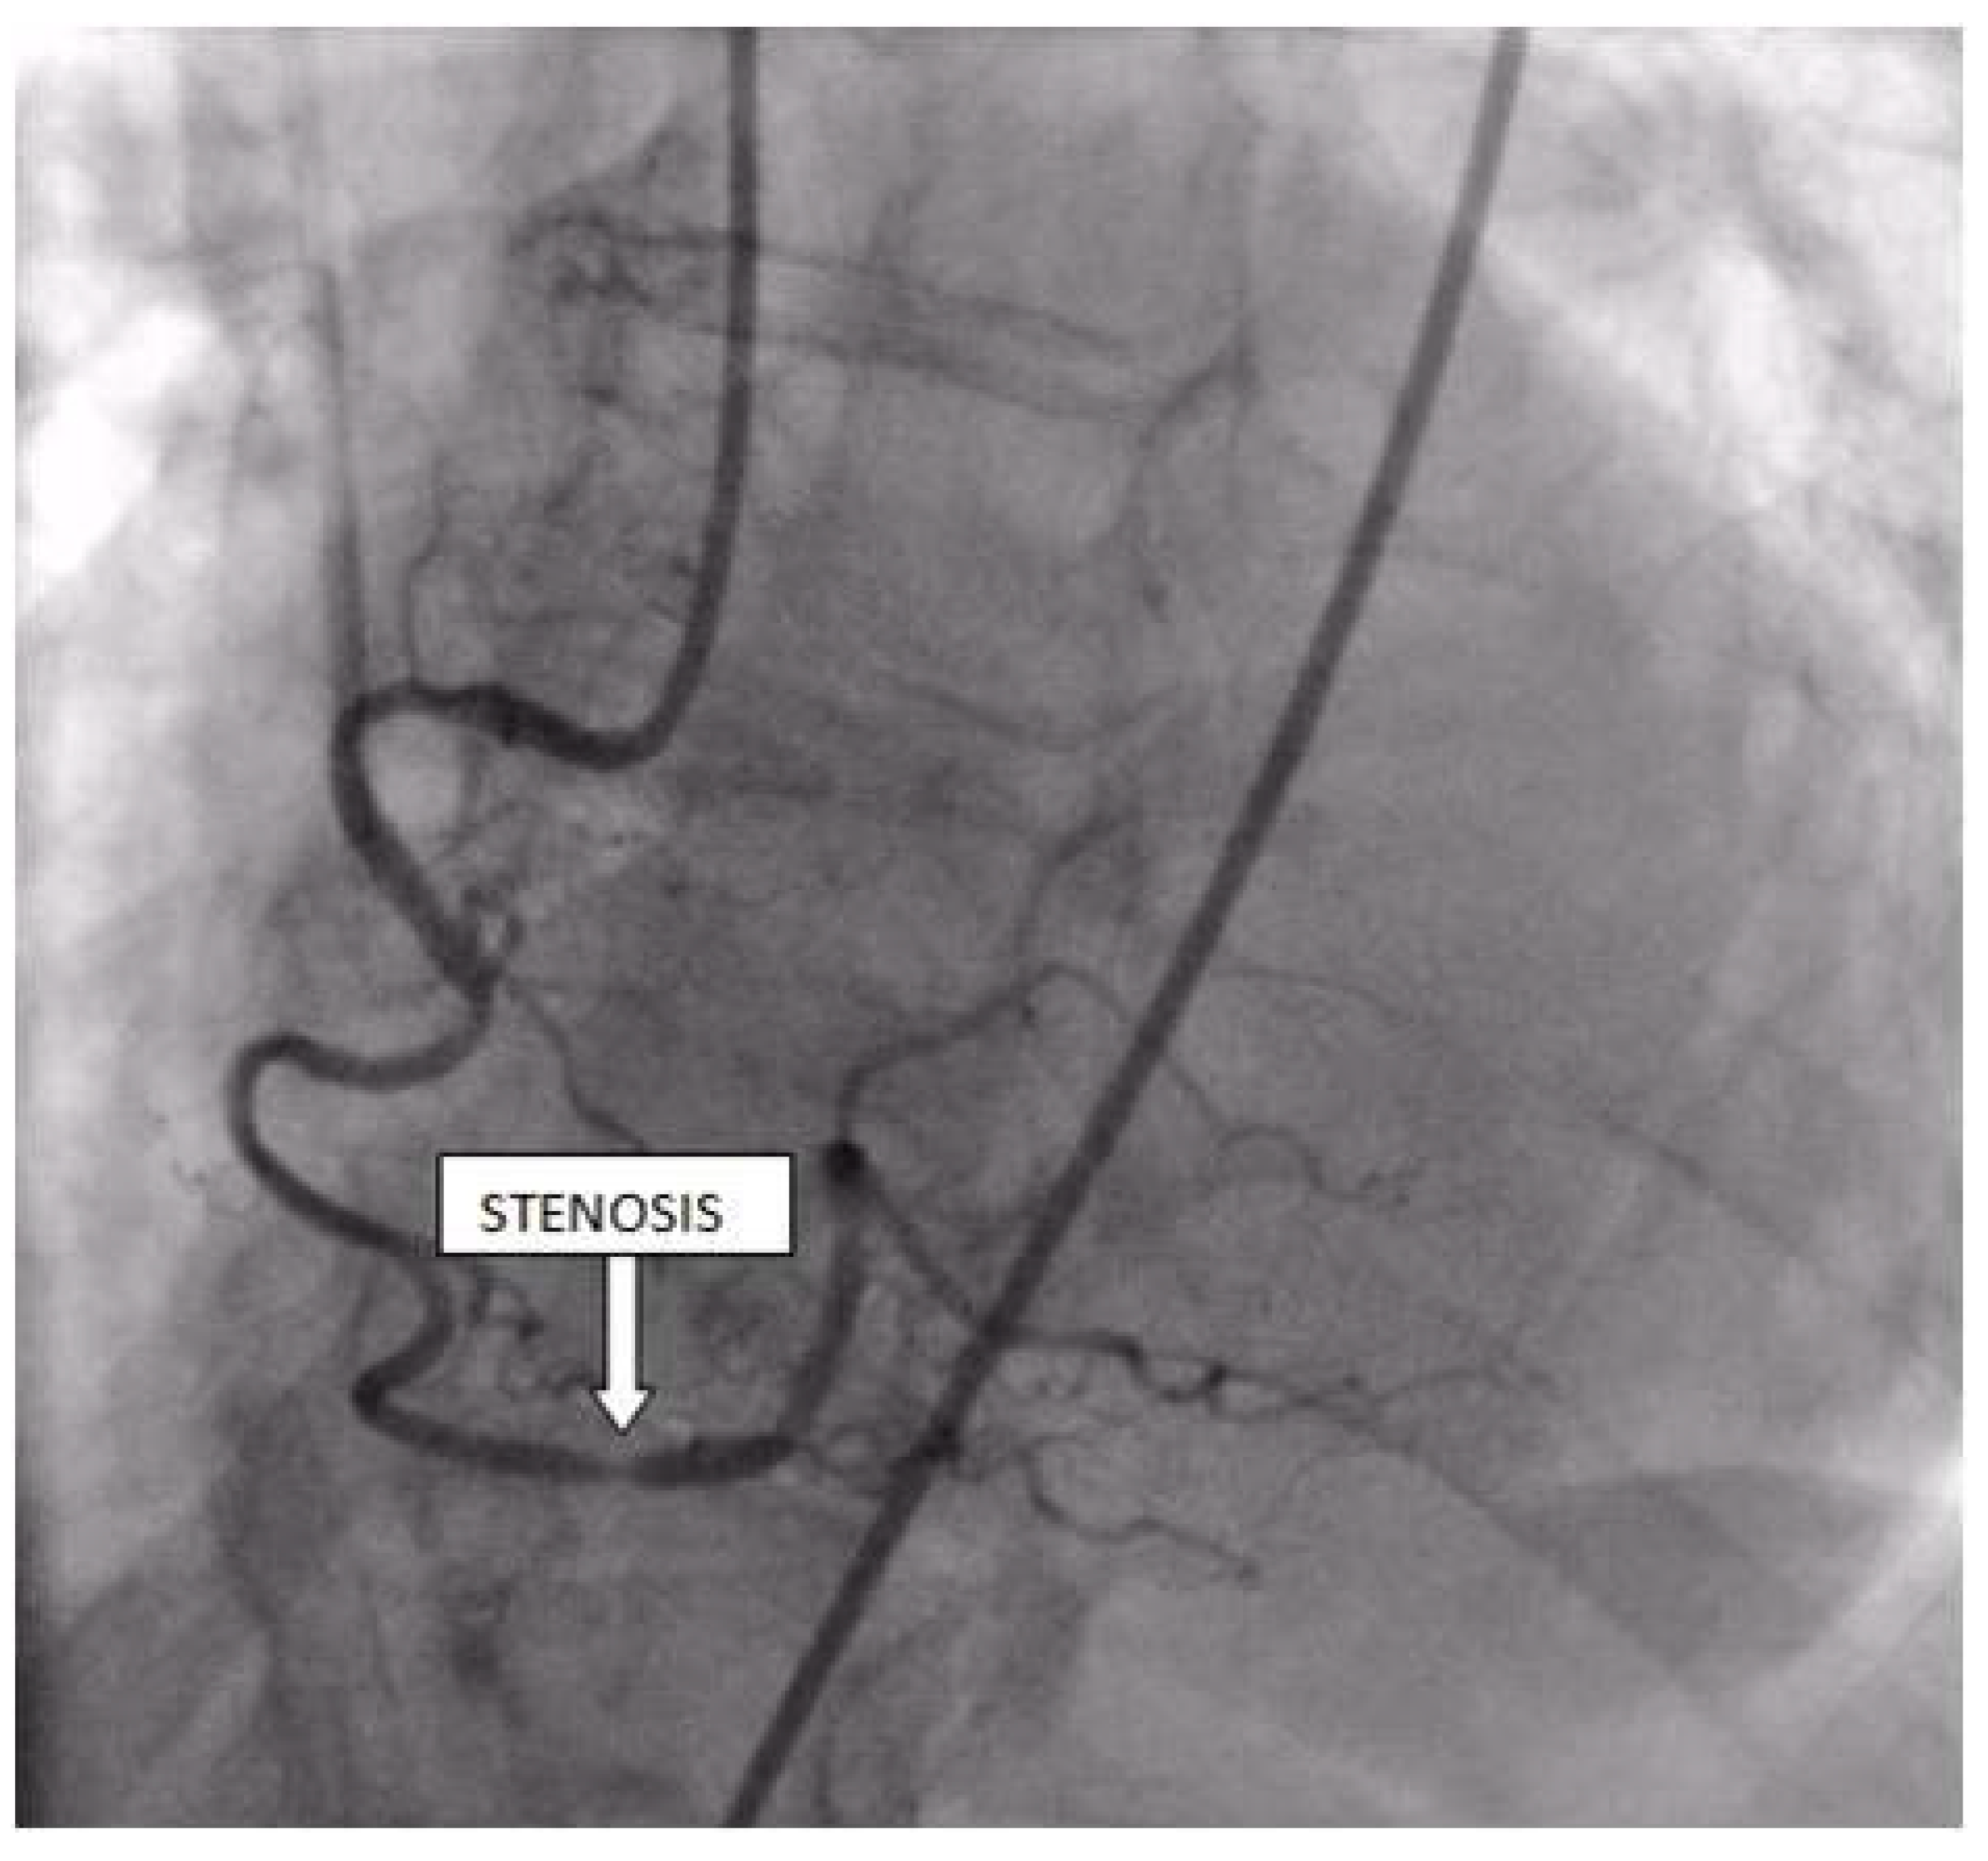

Coronary angiography was performed, showing the left coronary artery (LCA) was without significant lesions (Figure 6). On the right coronary artery (RCA), a subocclusive lesion was registered in the distal segment (Figure 7). Initially, it was thought to be a spasm, but the lesion persisted even after administering nitroglycerin intracoronary. Therefore, a primary percutaneous coronary intervention (pPCI) was performed with the implantation of a drug-eluting stent 16 × 25 mm (Boston Scientific, Marlborough, MA, USA) in the RCA, achieving the optimal result of the intervention (Figure 8).

Figure 7.

Coronary angiography registered a subocclusive lesion in the distal segment of the right coronary artery.